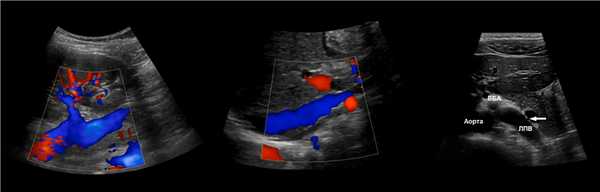

ППА проходит позади нижней полой вены. ЛПВ проходит через «пинцет» между аортой и верхней брыжеечной артерией. Иногда встречается кольцевидная ЛПВ, тогда одна ветвь располагается впереди, а другая — позади аорты.

Рисунок. В режиме ЦДК на продольном (1) и поперечном (2) срезах от аорты отходят ППА и ЛПА. Сосуды направляются к воротам почки. Кпереди от почечной артерии располагается почечная вена (3).

Рисунок. Почечные вены впадают в нижнюю полую вену (1, 2). Аортомезентериальный «пинцет» может сдавливать ЛПВ (3).

Задача. На УЗИ левая почечная вена расширена (13 мм), участок между аортой и верхней брыжеечной артерией заужен (1 мм). Кровоток в зоне стеноза с высокой скоростью (320 cм/сек), реверс кровотока в проксимальном сегменте. Заключение: Компрессия левой почечной вены аортомезентериальным «пинцетом» (синдром Щелкунчика).